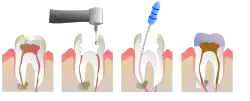

Unter einer Wurzelkanalbehandlung versteht man in der Zahnmedizin eine Therapie mit dem Ziel, einen Zahn zu erhalten, dessen Pulpa (im Volksmund: „Zahnnerv“) vital, aber irreversibel entzündet oder devital (abgestorben) ist. Dabei wird das vitale oder devitale Pulpengewebe aus dem Wurzelkanal entfernt, der Wurzelkanal erweitert und dabei das den Wurzelkanal umgebende infizierte Wurzeldentin durch Herausfeilen entfernt. Abschließend wird der Wurzelkanal gefüllt. Die Wurzelkanalbehandlung ist Teil der Endodontie, die wiederum zur konservierenden Zahnheilkunde gehört.

- Ist der Zahn vital und die Pulpa irreversibel geschädigt, wird eine Vitalexstirpation durchgeführt. Nach einer Lokalanästhesie wird die Pulpa mit einer Exstirpationsnadel entfernt und das System der Wurzelkanäle mechanisch durch eine Aufbereitung gereinigt. Dabei wird mit Feilen mit aufsteigendem Durchmesser die Kanalwand ausgefeilt. Nach weiteren Reinigungsprozessen mittels Natriumhypochloritlösungen wird der Zahn mittels einer Wurzelkanalfüllung wieder verschlossen.

- Ist der Zahn bereits devital, ist das Ziel der Behandlung die Entfernung der gangränösen Pulpa und der Keime aus dem Zahninneren. Nach der Eröffnung des Zahnes wird auch hier – wie bei der Vitalexstirpation – das System der Wurzelkanäle ausgefeilt und gereinigt.

Praktische Durchführung

Zugangskavität

Nach ggf. Anlegen von Kofferdam wird zunächst ein Zugang zum Kanalsystem geschaffen. Dieser muss einerseits groß genug sein, um die Behandlung unter guter Sicht durchführen zu können, andererseits aber auch nicht zu groß, um einen unnötigen Verlust von gesunder Zahnsubstanz zu vermeiden.

Reinigung

Nach einer Lokalanästhesie erfolgt die Längenbestimmung des Wurzelkanals oder der -kanäle (anhand eines Röntgeneinzelbilds in Verbindung mit speziellen Messnadeln oder auf elektrischem Weg durch Endometrie). Anschließend werden die Kanäle mit Handfeilen oder maschinell angetriebenen rotierenden Instrumenten konisch erweitert („aufbereitet“). Durch Spülungen mit verschiedenen Lösungen, wie z. B. NaOCl, 3-prozentige H2O2-Lösung, EDTA oder CHX, werden Verunreinigungen aus den Kanälen entfernt, die Schmierschicht beseitigt und Mikroorganismen bekämpft. Mittels Laser kann vor der Abfüllung der Kanäle zusätzlich zu den üblich verwendeten Spüllösungen eine Desinfektion erfolgen. Die Spüllösungen können durch Ultraschall aktiviert werden, um die Wirkung zu verstärken. Auf diese Weise können auch Kanalverzweigungen und infizierte Dentinbereiche desinfiziert werden, die einer instrumentellen Aufbereitung nicht zugänglich sind. Auf Endodontie spezialisierte Zahnärzte verwenden bei der Wurzelkanalbehandlung ein Operationsmikroskop, das mit seiner zusätzlichen Lichtquelle mit koaxialem Licht und der Vergrößerung das Auffinden und Betrachten der Kanaleingänge erleichtert.

Ausformung

Zur füllungsgerechten Aufbereitung des Kanalsystems hat es sich bewährt, die Kanaleingänge zuerst von koronal nach apikal mit Gates-Glidden-Bohrern koronal zu erweitern. Die weitere Aufbereitung des Kanalsystems kann entweder mit einer apikal-koronalen Methode wie der Step-back-Technik oder bei gekrümmten Kanälen mit einer koronal-apikalen Methode wie der Crown-down-Technik erfolgen.[3] Die Wurzelkanalinstrumente dienen neben dem Dentinabtrag (im Sinne einer Reinigung) vorrangig zur Formgebung der Wurzelkanalhohlräume. Die Instrumente schaffen durch die Bearbeitung der Wurzelkanalwände Platz, um die Effektivität der Spüllösungen zu verbessern und um ein definiertes Profil zum vorhersehbaren Verschluss zu präparieren.

Füllung

Die Wurzelfüllung gehört zu den Zahnfüllungen. Nach der Reinigung und Ausformung der Wurzelkanäle werden die Hohlräume gefüllt. Dies erfolgt überwiegend mit Guttapercha und einem Dichtzement, einem Versiegler (engl. „Sealer“). Die Wurzelfüllung sollte möglichst viel Guttapercha und möglichst wenig Sealer enthalten, weil die Guttapercha das biokompatiblere und stabilere Material darstellt.

Die Wurzelfüllung kann klassisch mittels eines Zements und eines Guttaperchastifts erfolgen (Ein-Stift-Methode) oder mittels lateraler Kondensation, wo zusätzlich noch weitere Guttaperchastifte eine dichtere Wurzelfüllung ermöglichen. Es gibt des Weiteren die Möglichkeit, mittels thermischer Wurzelfüllungstechniken den Zahn abzufüllen. Dabei wird ein Guttaperchastift erwärmt und dann in den Kanal eingebracht, wodurch die Möglichkeit besteht, durch Verflüssigung des Materials in die Aufästelung des Wurzelkanals an der Wurzelspitze in die kleinen Lumen einzudringen. Hier kann es zu einem Herauspressen des Sealermaterials um die Wurzelspitze kommen (Puff). Zudem besteht die Möglichkeit, einen Stift zuerst einzubringen, ihn dann im Kanal zu erwärmen und abzutrennen („Downpack“) und den Rest des Kanals mit flüssiger Guttapercha (Backfill) aufzufüllen. Für die zuletzt genannte Technik ist ein Operationsmikroskop zur besseren Sicht von Vorteil. Zusätzlich bietet das Operationsmikroskop die Möglichkeit, weitere kleinere Kanäle im Zahn aufzufinden oder Perforationen im Kanal mit besonderen Materialien zu decken.